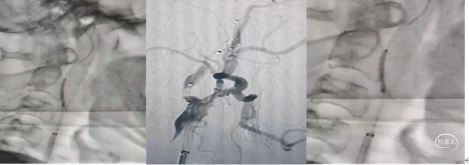

8Fguiding到达C1段支撑070银蛇中间导管裸奔边上行边抽吸,抽出部分血栓,造影显示到血流达到C6段。

术中边推进导管边抽吸,抽出部分血栓,造影显示到血流达到C6段。

1、微导管到位:微导丝通过M1段艰涩困难,再次偿试通过M1段到达M2。携带微导管到达M2段,微导管造影显示远端有正向血流,在真腔内。下图1

2、支架释放:通过027微导管释放6X30mm 通桥蛟龙支架,静置5分钟后微造影,大脑中未显影,未见首过效应考虑血栓负荷较大。大脑前有血流。下图2

4、中间导管收拢支架尾部一体回撤:中间导管跟进至M1段收拢支架尾部下,负压踹马桶抽吸中间导管,缓慢一体回撤支架和中间导管,一次取出长约3.5cm黯红色血栓。

造影显示:

大脑中动脉畅通,远端血流达3级。但分叉以远分支似有少量血栓。考虑6x30m支架放置M2段过大,未再进行远端分支取栓,经导引导管给予替罗非班6ml推注。结束手术。

手术过程:经股动脉穿刺,置入8F动脉鞘术中造影左侧颈内动脉重度狭窄,颈内血流迟缓。

微导丝携带微导管尝试通过狭窄到达M1段微造影远端血管通畅。通过6F长鞘颈总动脉造影颈内动脉全程通畅,仅仅为颈内起始部重度狭窄。考虑颈内动脉ICAS病变,静脉溶栓再通但不畅。微导丝携带微导管通过狭窄部位改善了血流。

球囊扩张血管成形 3mmx15、4.5mmx15球囊扩张颈内动脉狭窄部位,造影显示狭窄改善,全程血流通畅且快速,Ⅰ未植入支架,推注替罗非班10mL,造影未见远端血管血栓逸逃征象,结束手术。药物治疗观察必要时Ⅱ期支架植入血管成形。

1、椎动脉支架植入:术中造影显示:左椎动脉狭窄约90%。经股动脉入路在左锁骨下动脉置入8F导引导管,微导丝携带2*20mm冠脉球囊预扩张左椎动脉开口,微导丝导引4.5x15mm钴基合金雷帕霉素洗脱支架在12个大气压下植于左侧椎动脉开口,造影显示支架位置良好,未见明显残余狭窄。

8F导引导管置于颈总动脉远端建立通路,微导丝携带2mmⅩ20冠脉球囊在10个大气压下扩张狭窄部位,在C1远端置入栓塞保护器,沿保护器导丝输送4*30球囊进行预扩张后,沿保护伞导丝输送6~8~40mm自膨支架,铆定狭窄位置后释放支架于狭窄部位,造影显示支架位置良好,夹层消失,未见明显残余狭窄。

回撤5F中间导管于颈总动脉造影显示颈内动脉起始段重度狭窄。(下图1)

在C1段置入5mm保护伞,用3mm和4mm球囊扩张狭窄部位,但撤出球囊后狭窄略有改善。(下图2)

置入6~8~40mm自膨支架,支架位置良好,残余狭窄约30%。(下图3)

回撤导管与颈总动脉造影支架位置良好,远端大脑中动脉显影良好,分叉部无明确血栓征象。可能经替罗非班推注和血管通畅后逃逸的小血栓溶解了。再通后流动的血液就是最好的溶栓剂。